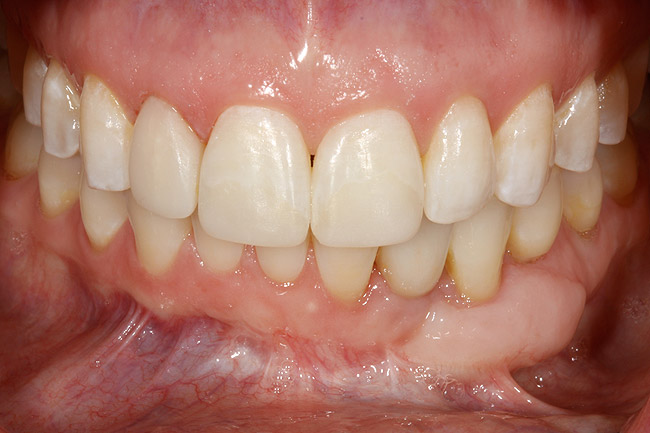

Figure 24  Definitive restoration of tooth No. 23.

Figure 24

Figure 25  Postoperative view of definitive restorations teeth Nos. 7 to 9 and No. 23.

Figure 25

Following the first goal of orthodontia—moving tooth No. 22 to a proper functional and anatomical position—a periodontal reevaluation was performed, demonstrating an improvement in short- and long-term tooth prognosis. At this time, the decision was made to abort continual extrusion of teeth Nos. 21 and 22, although some attachment level discrepancy remained between Nos. 21 and 22 (Figure 14). Implant diagnostics ensued and included mounted study models and a diagnostic wax-up. A scanning appliance was created to demonstrate the desired prosthetic outcome requirements, and the patient was referred for computed tomography (CT) scans. CT scan assessment demonstrated successful orthodontically directed GBR to allow implant placement (Figure 15 through Figure 16). Only minor GBR therapy would be needed and could be accomplished simultaneously with implant installation. Guided implant placement occurred, using an open flap approach (Figure 17). During surgery, root dehiscences were noted on teeth Nos. 21, 22, 24, and 25, as well as the anticipated dehiscence following implant placement at No. 23 (Figure 18). A positioning reference (index) was secured after implant placement to facilitate a provisional prosthesis at stage II surgery. Cortical perforations then were placed adjacent to the implant to encourage angiogenesis (Figure 18), and mineralized freeze-dried bone allograft enhanced with platelet-derived growth factor was placed over the dehiscences for purposes of guided tissue regeneration and GBR (Figure 19). A highly resorbable collagen membrane was placed to stabilize the allograft. The flap was coronally repositioned, and primary-intention wound healing was achieved (Figure 20 and Figure 21). Following 4 months of stage I surgery, implant uncovery and immediate provisionalization were performed in conjunction with connective tissue grafting. Final orthodontic tooth movement then ensued, using the implant as anchorage to optimize end-tooth movements, interroot separation, and the cuspid-protected occlusal scheme. A final impression then was secured, and a zirconia abutment (Figure 22) with an all-ceramic restoration was fabricated for the prosthetic phase completion of No. 23 (Figure 23 through Figure 25).

This case illustrates how to manage dentoalveolar ridge destruction, using orthodontics, periodontics, and restorative dentistry to idealize the occlusal scheme, develop an ideal implant site with orthodontics, and enhance the dentoalveolar ridge dimensions surgically with bone graft materials. Finally, it demonstrates how to restore proper tooth contours through minimal restorative dentistry with bonding and a single-unit, implant-supported crown.